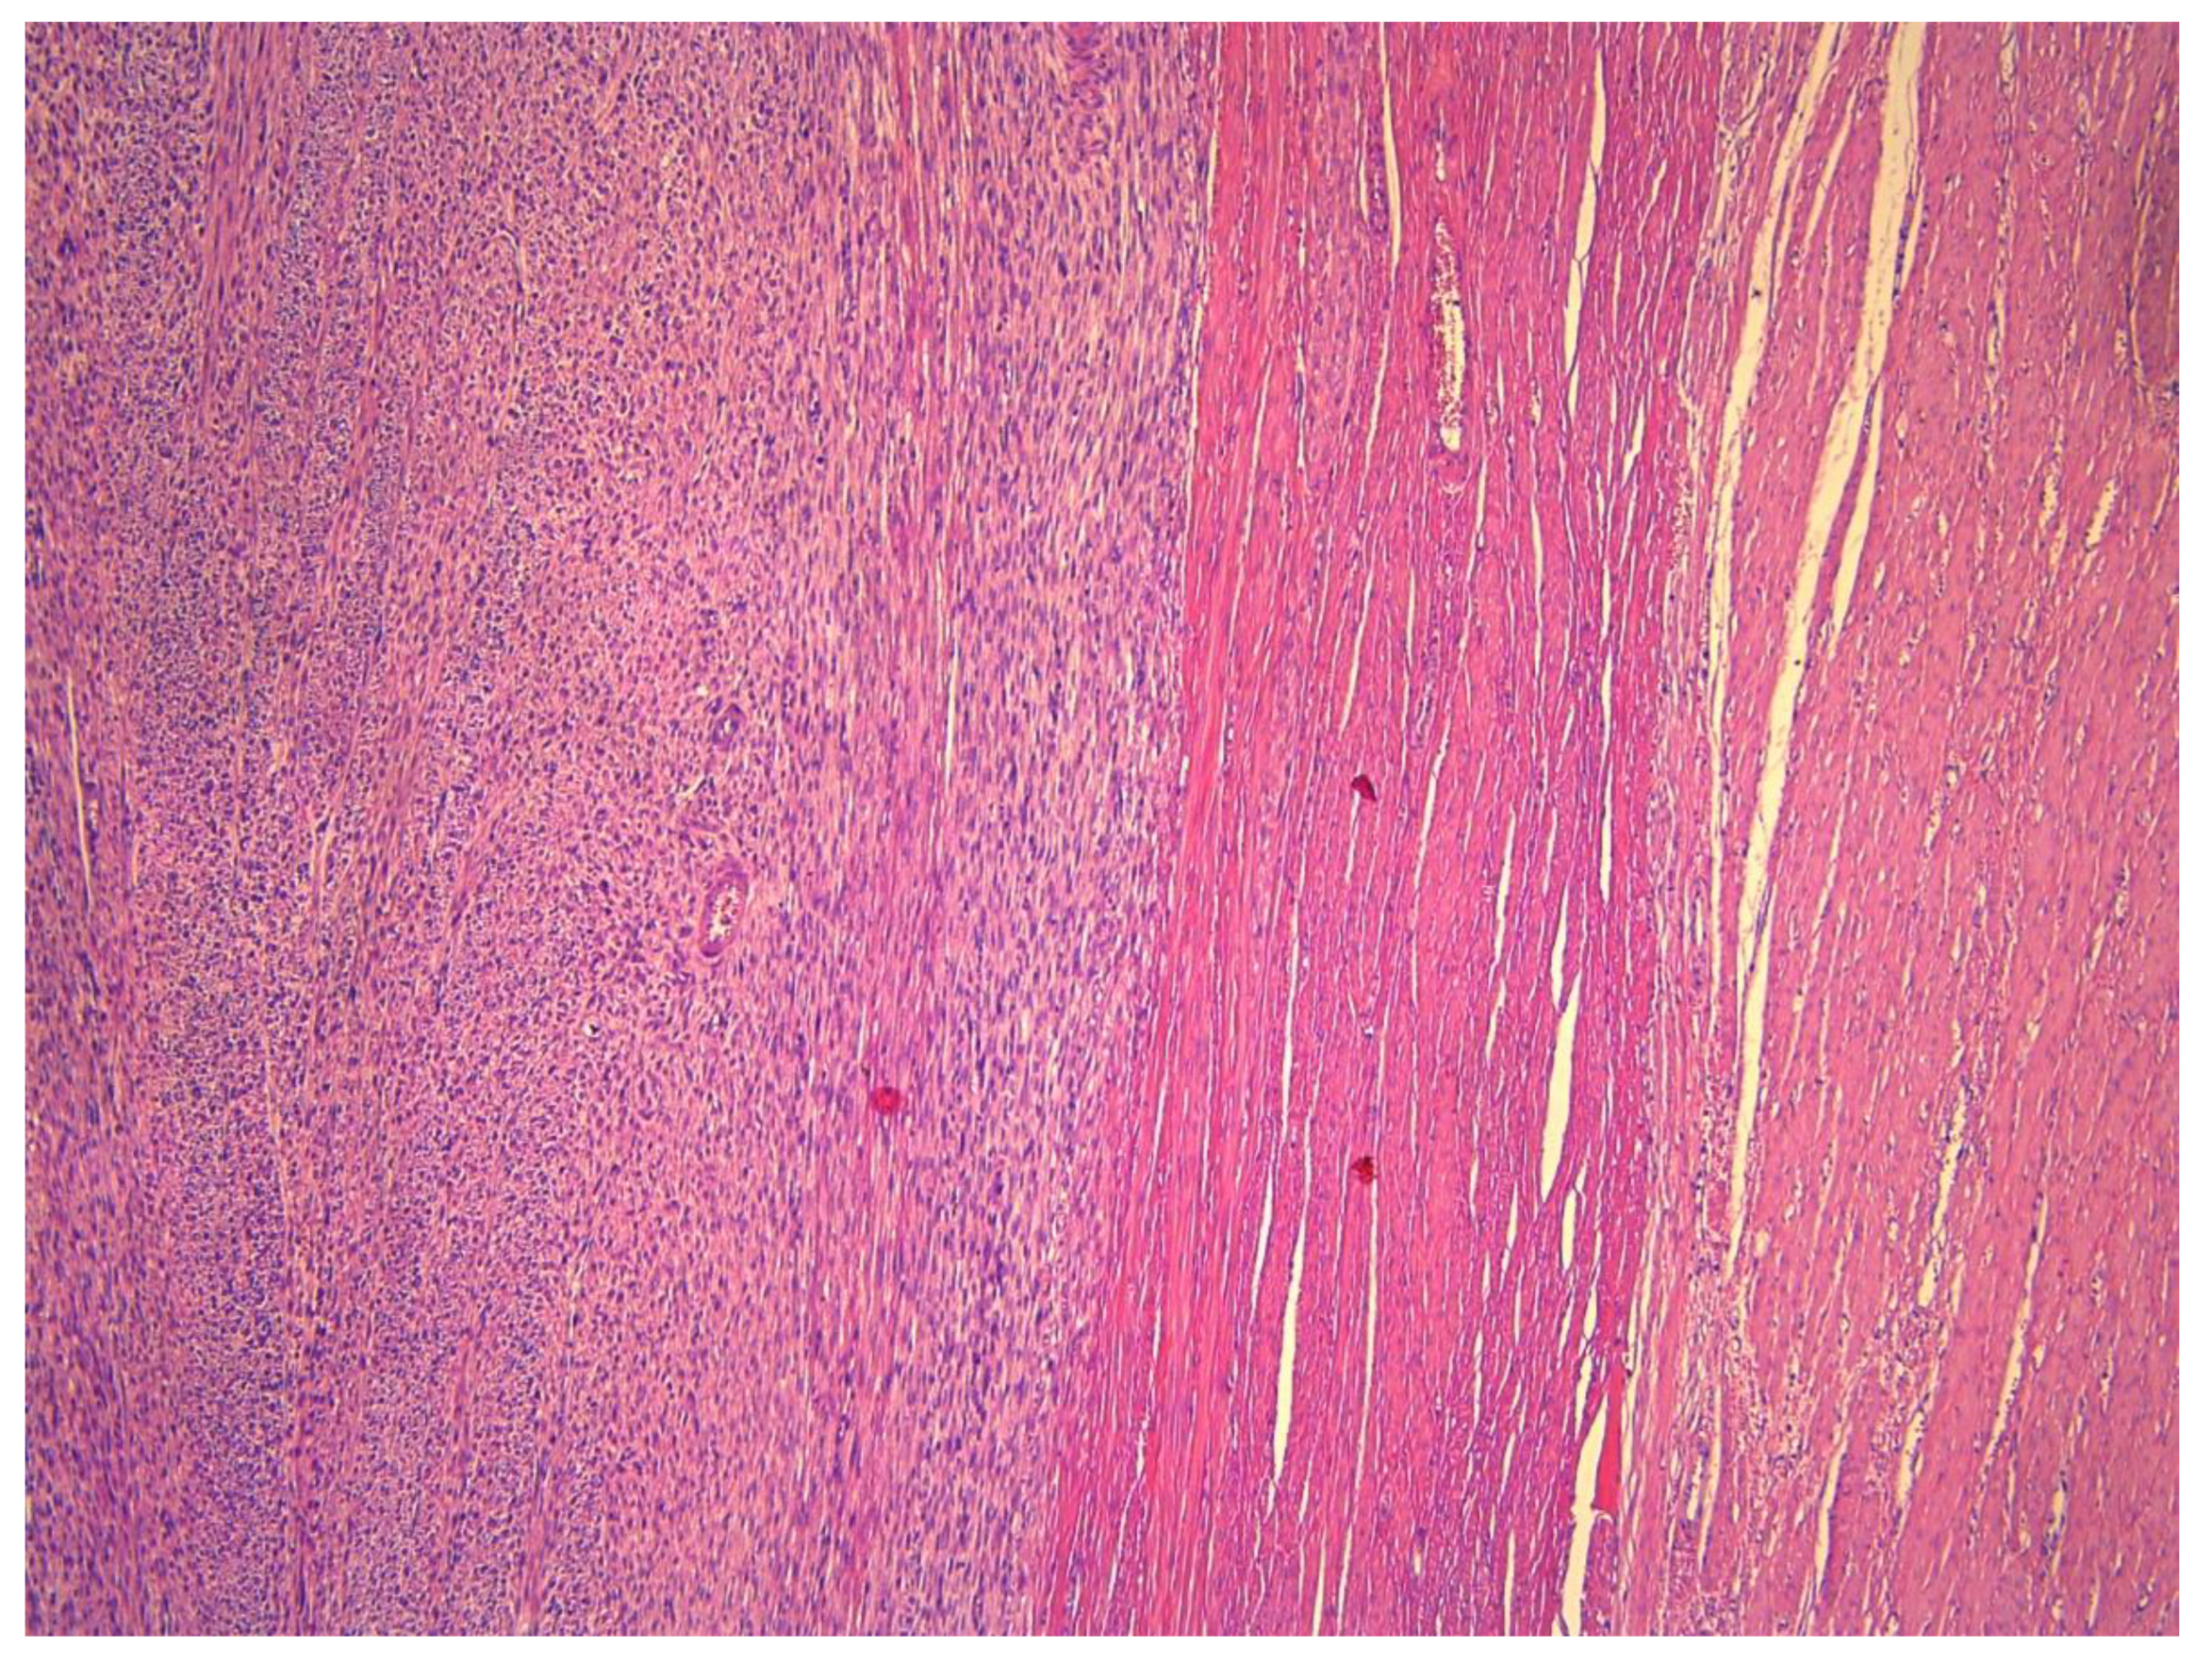

Macroscopically, STUMPs resemble fibroids and, thus, have a well-circumscribed and non-encapsulated appearance (Figure 1); however, sometimes the borders can be pushing or even focally permeative (Figure 2). The cut surface is usually tan-white, firm, and whorled. Areas of infarction, hemorrhage, and myxoid change can be apparent. The median size is 6.7 cm (range: 2.5–12.2 cm) [7]. Extensive sampling of these tumors is needed, specifically if myxoid areas are present. Microscopically, STUMPs are characterized by interlacing fascicles of spindle cells with cigar-shaped nuclei; however, the morphological features can vary widely (Figure 3).

Figure 3.

Smooth Muscle Tumor of Uncertain Malignant Potential (STUMP). (A) Hematoxylin and Eosin (H & E)-stained section at 40× magnification showing bundles of smooth muscle cells. (B) H & E-stained section at 100× showing tumor cells with diffuse moderate-to-severe atypia. (C) H & E section at 200× revealing spindled cells showing atypia and pleomorphism. (D) H & E section at 400× depicting atypia and occasional mitosis. There was no tumor necrosis and mitotic count was less than 10/10 HPFs, consistent with the diagnosis of STUMP.